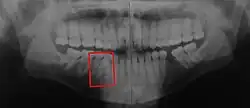

Unter Hyperdontie (auch Hyperodontie, Polyodontie oder Polydontie) (von altgriech. ὕπέρ „über-“ und ὀδόντος „mit Zähnen versehen“)[1] versteht man eine Zahnüberzahl. Für das menschliche Gebiss heißt das, im Milchgebiss sind mehr als 20 bzw. im bleibenden Gebiss sind mehr als 32 Zähne vorhanden.[2] Eine Besonderheit ist im Abschnitt unechte Hyperdontie erläutert. Bereits entfernte Zähne sind mitzuzählen. Im Milchgebiss sind Hyperdontien selten.

Morphologisch betrachtet können überzählige Zähne in regelrechter oder irregulärer Zahnform (z. B. Mesiodens), als Doppel- oder Mehrfachgebilde, als getrennte Doppelanlagen (Zwillingszähne), als Verwachsungen oder als Verschmelzungen auftreten. Zahnverwachsungen oder -verschmelzungen können so weit gehen, dass das Gebilde wie ein übermäßig großer Zahn aussieht. Weil solche Mehrfachgebilde vornehmlich im Frontzahnbereich auftreten, ergeben sich in diesen Fällen auch ästhetische Probleme. Gehäuft tritt die Hyperdontie bei Lippen-, Kiefer-, Gaumenspalten auf.[9]

- Mesiodentes können bei genetischer Fixierung familiär gehäuft auftreten. Diese Form der Hyperdontie macht fast die Hälfte aller überzähligen Zähne aus.